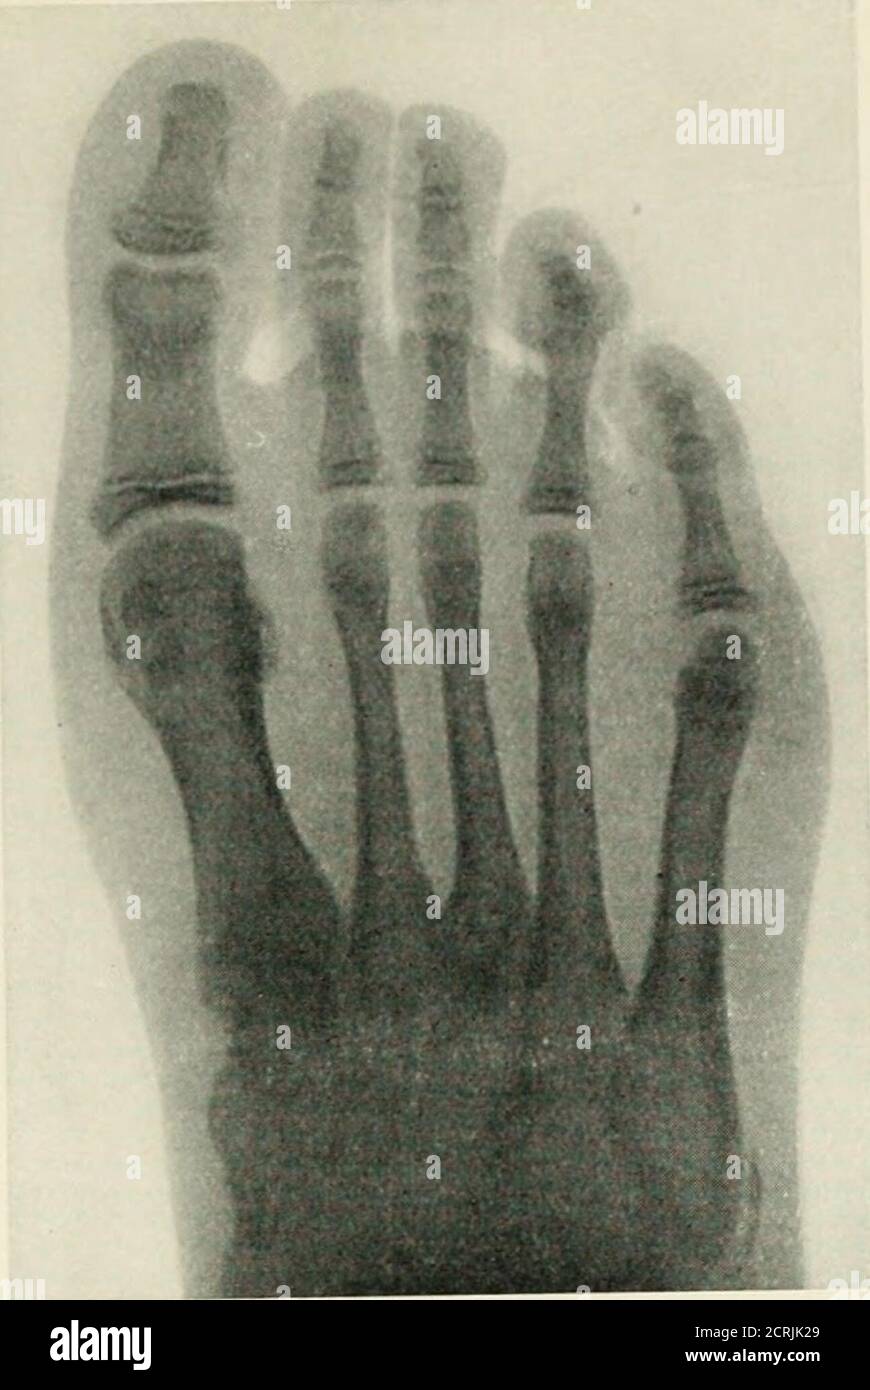

Tabelle crescita fetale CRL BPD CC CM CA FL feto sales, Feto a 5 settimane immagini e fotografie stock ad alta risoluzione Alamy sales, Tabelle fetali sales, Image of feto in posizione parto podalica con piede e mano caduto sales, Lunghezza piede bambino e numero scarpa Nostrofiglio sales, 16 settimana di gravidanza ecografia lunghezza e peso del feto sales, Piedi in gravidanza attenzione all alluce valgo Alluce valgo innovazione nell operazione chirurgica intervento mini invasivo sales, 20 settimana di gravidanza sintomi e sviluppo del bambino sales, Med 2000 eco sales, Feto del modello Baby Bambino strati Kind stellungen urologie modello a grandezza naturale Amazon Commercio Industria e Scienza sales, Trentesima Settimana Di Gravidanza Settimana 30 sales, La gravidanza mese per mese sviluppo fetale e cambiamenti nella madre sales, Ecografia Morfologica Dr Annona sales, PIEDE TORTO ilpiedetorto sales, Modello Anatomico Dell organo Neonatale Dei Neonati Del Cordone Ombelico Addominale Del Feto Placentale Modello Anatomico Per L insegnamento Della Classe studenti Modelli Medici E Materiali Educativi ... sales, Sviluppo del feto sales, Lo Sviluppo dell Embrione Feto sales, Omessa diagnosi di spina bifida del feto sales, Le Fasi della Gravidanza con la Frutta Donkid sales, Feto a 15 settimane immagini e fotografie stock ad alta risoluzione Alamy sales, Tabelle crescita fetale CRL BPD CC CM CA FL feto sales, 32 settimane di gravidanza peso feto e quanto manca al parto sales, PIEDE TORTO ilpiedetorto sales, 4.036 Feto High Res Illustrations Getty Images Gravidanza Neonato Embrione sales, Immagine prenatale 5D a 31 33 settimane di gravidanza emoxione sales, Modello di Feto per Bambini di 9 Mesi Bacino Femminile di Gravidanza con Organi Rimovibili Anatomia della Sezione Pelvica della Gravidanza Umana Modello Didattico Anatomico Amazon Commercio Industr... sales, Trentaduesima settimana di gravidanza Pampers sales, Trentottesima Settimana Di Gravidanza Settimana 38 sales, Tabelle fetali sales, Niente cesareo per non rimanere oltre il turno sales, Pressioni sull addome della partoriente e lesioni al feto sales, PIEDE TORTO ilpiedetorto sales, Tappetino di misurazione per misuratore di lunghezza del corpo del bambino neonato righello di crescita del bambino misura del corpo infantile AliExpress sales, Radiografia radioterapia e radioterapia FLG. 111. mostrando le ossa alla caviglia e al piede con epifisi edate a cui si uniscono con le diafisie. Interamente composto dall epifisi inferiore del fibula... sales, Oligoidramnios cause sintomi diagnosi terapie conseguenze rischi per il feto e la madre MEDICINA ONLINE sales.

Tabelle crescita fetale CRL BPD CC CM CA FL feto sales, Feto a 5 settimane immagini e fotografie stock ad alta risoluzione Alamy sales, Tabelle fetali sales, Image of feto in posizione parto podalica con piede e mano caduto sales, Lunghezza piede bambino e numero scarpa Nostrofiglio sales, 16 settimana di gravidanza ecografia lunghezza e peso del feto sales, Piedi in gravidanza attenzione all alluce valgo Alluce valgo innovazione nell operazione chirurgica intervento mini invasivo sales, 20 settimana di gravidanza sintomi e sviluppo del bambino sales, Med 2000 eco sales, Feto del modello Baby Bambino strati Kind stellungen urologie modello a grandezza naturale Amazon Commercio Industria e Scienza sales, Trentesima Settimana Di Gravidanza Settimana 30 sales, La gravidanza mese per mese sviluppo fetale e cambiamenti nella madre sales, Ecografia Morfologica Dr Annona sales, PIEDE TORTO ilpiedetorto sales, Modello Anatomico Dell organo Neonatale Dei Neonati Del Cordone Ombelico Addominale Del Feto Placentale Modello Anatomico Per L insegnamento Della Classe studenti Modelli Medici E Materiali Educativi ... sales, Sviluppo del feto sales, Lo Sviluppo dell Embrione Feto sales, Omessa diagnosi di spina bifida del feto sales, Le Fasi della Gravidanza con la Frutta Donkid sales, Feto a 15 settimane immagini e fotografie stock ad alta risoluzione Alamy sales, Tabelle crescita fetale CRL BPD CC CM CA FL feto sales, 32 settimane di gravidanza peso feto e quanto manca al parto sales, PIEDE TORTO ilpiedetorto sales, 4.036 Feto High Res Illustrations Getty Images Gravidanza Neonato Embrione sales, Immagine prenatale 5D a 31 33 settimane di gravidanza emoxione sales, Modello di Feto per Bambini di 9 Mesi Bacino Femminile di Gravidanza con Organi Rimovibili Anatomia della Sezione Pelvica della Gravidanza Umana Modello Didattico Anatomico Amazon Commercio Industr... sales, Trentaduesima settimana di gravidanza Pampers sales, Trentottesima Settimana Di Gravidanza Settimana 38 sales, Tabelle fetali sales, Niente cesareo per non rimanere oltre il turno sales, Pressioni sull addome della partoriente e lesioni al feto sales, PIEDE TORTO ilpiedetorto sales, Tappetino di misurazione per misuratore di lunghezza del corpo del bambino neonato righello di crescita del bambino misura del corpo infantile AliExpress sales, Radiografia radioterapia e radioterapia FLG. 111. mostrando le ossa alla caviglia e al piede con epifisi edate a cui si uniscono con le diafisie. Interamente composto dall epifisi inferiore del fibula... sales, Oligoidramnios cause sintomi diagnosi terapie conseguenze rischi per il feto e la madre MEDICINA ONLINE sales.